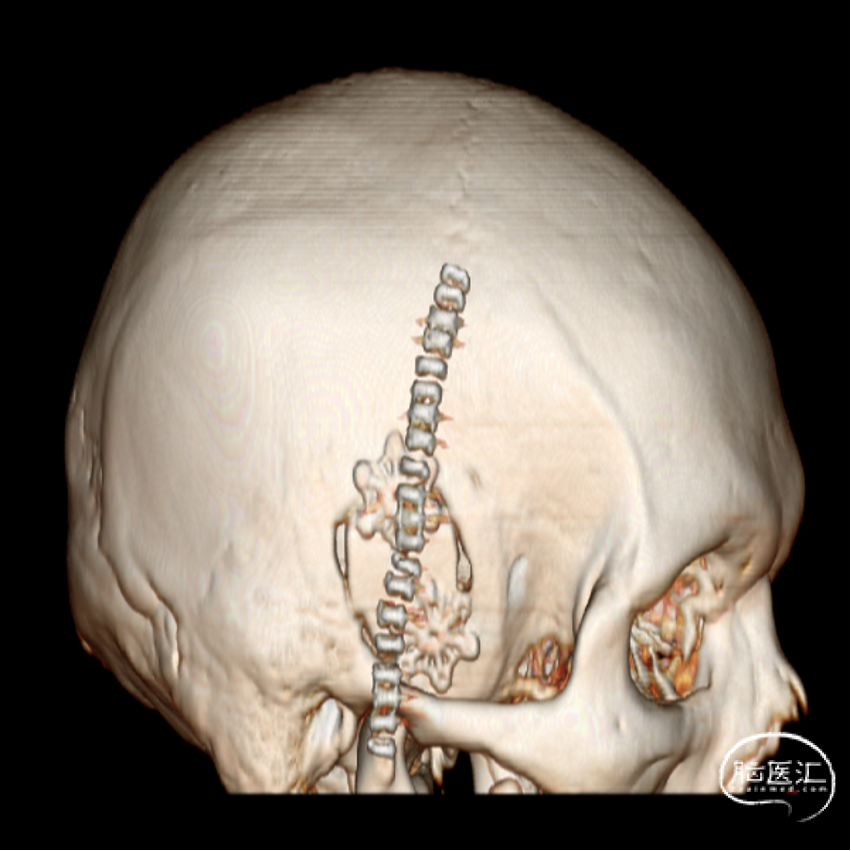

外院CT示:右侧颅底占位性病变,临近骨质部分吸收。